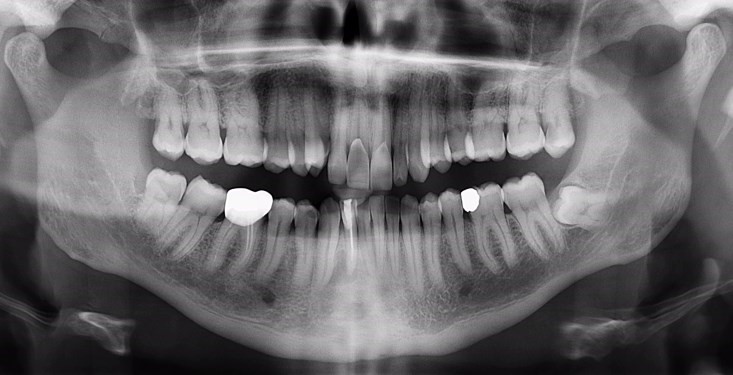

panoramique dentaire

Le cliché panoramique donne une vue d’ensemble des arcades dentaires, des maxillaires, des articulations et des sinus. Il est utilisé pour diagnostiquer un grand nombre de conditions pathologiques : infections, fractures des mâchoires, kystes et granulomes à la racine des dents, et certaines affections osseuses (maladie de Paget)…

On effectue aussi un panoramique dentaire pour évaluer la distribution des dents, la perte osseuse et les parodontites, ou encore pour visualiser l’ensemble des germes de dents chez l’enfant, pour définir son âge dentaire. Par ailleurs, il s’avère également utile pour décider du bien-fondé de la pose d’implants ou de la localisation des racines artificielles avant leur pose.